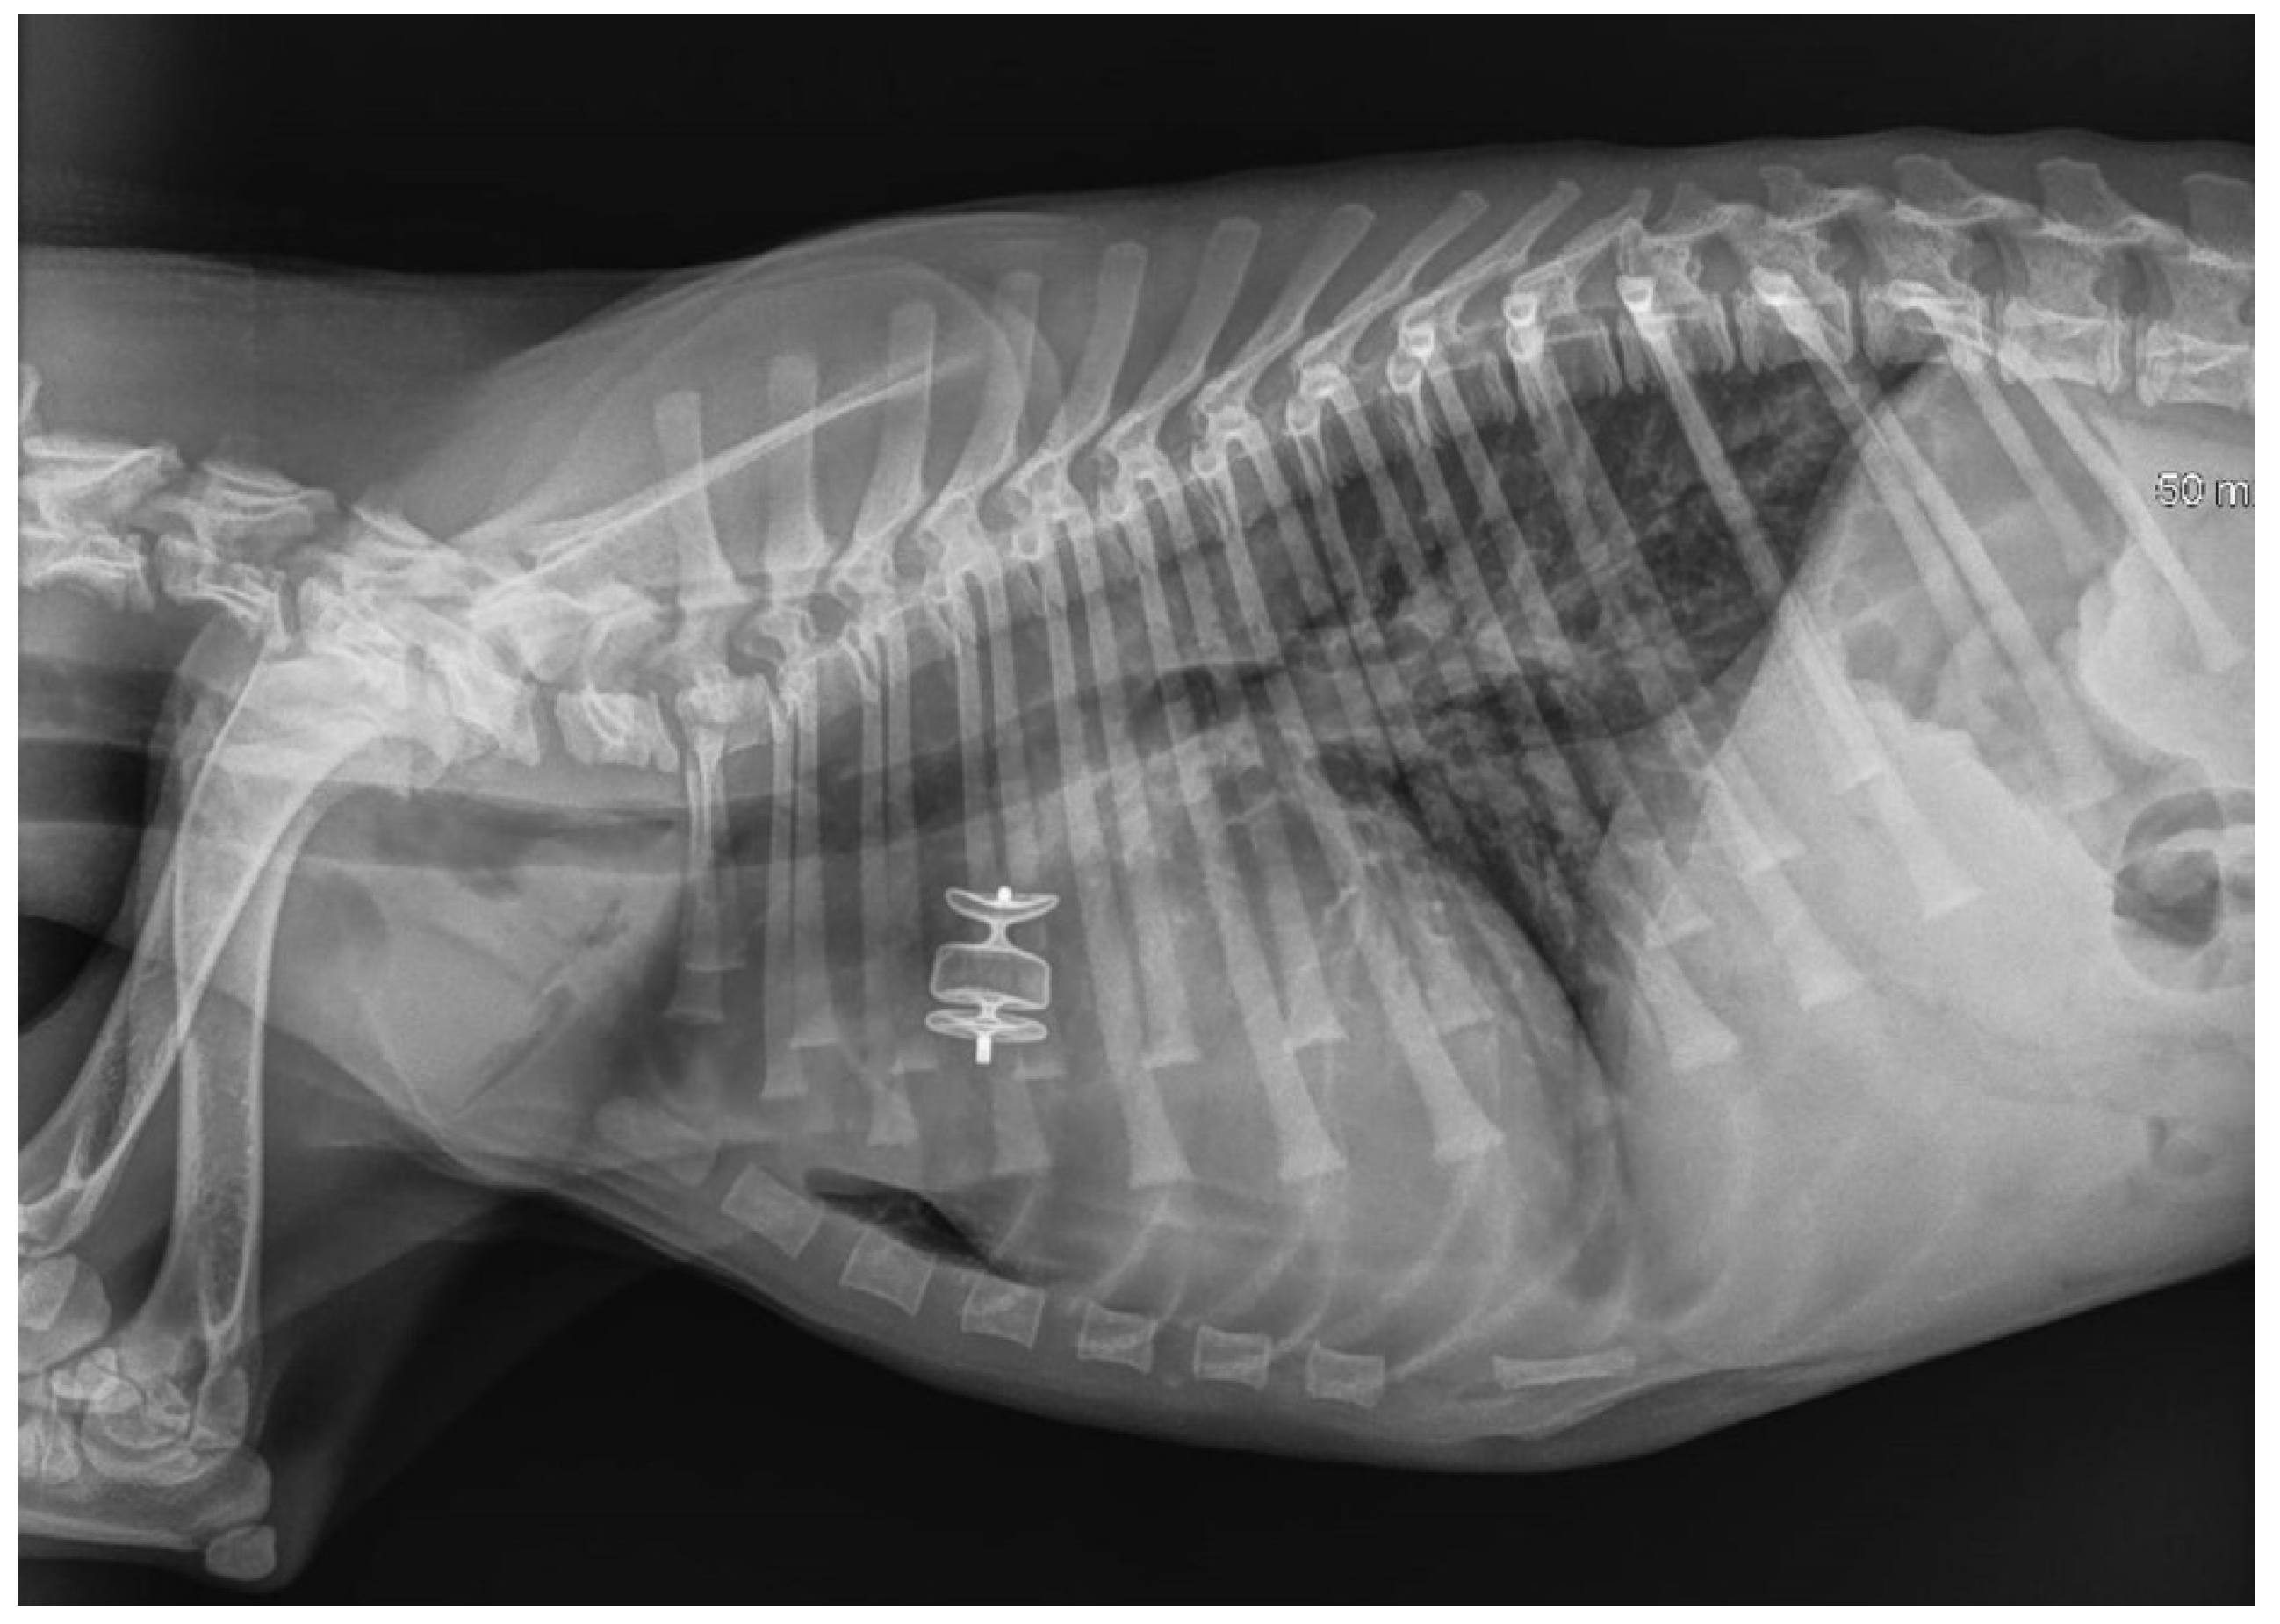

The AVP II device was then detached by counterclockwise rotation of the delivery wire. All catheters were then removed, and the right jugular vein was sutured with 4-0 monofilament polydioxanone absorbable suture (PDSII Ethicon) or ligated [30]. Post-operative thoracic radiography confirmed the correct placement of the device in all patients (Figure 6).

The thoracic radiographs performed before and just after the procedure showed a reduction in the cardiac silhouette as well as significant reduction of the over-circulation vascular pattern for all dogs (Figure 8, Figure 9, Figure 10, Figure 11 and Figure 12).

Figure 6. Immediate post-procedure right lateral thoracic radiograph (Case 3). The dog had pulmonary edema before the procedure, which was managed with medical treatment. The device is readily visible in situ. Mild pulmonary infiltrate was still observed in the lung field, especially the caudal lung lobes, after the procedure.